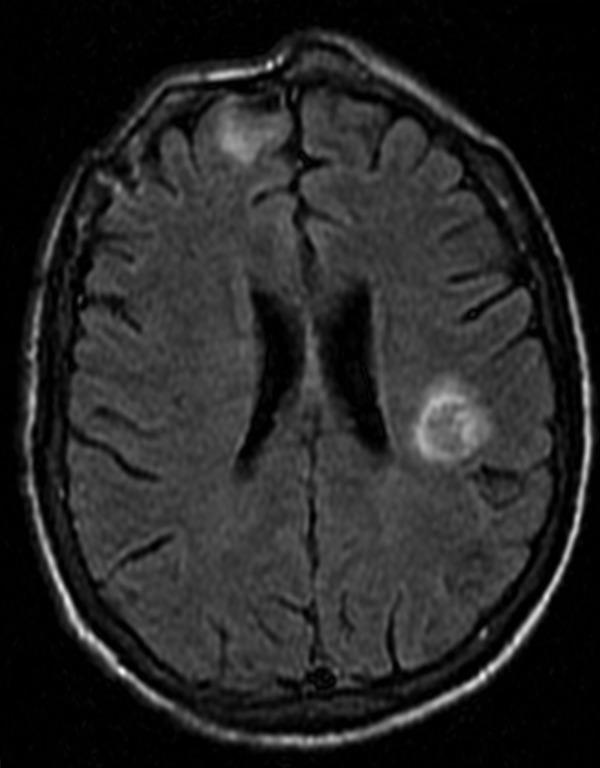

A 39-year-old male with newly diagnosed HIV had cavitary pneumonia initially attributed to Pneumocystis jirovecii but actually caused by Rhodococcus equi. After neurological deterioration, he was found to have intracerebral lesions caused by Toxoplasma gondii. This case underscores the inability to rely on the search for a unifying diagnosis (Ockham's Razor) in HIV-infected patients.

一名新诊断出感染艾滋病毒的39岁男性起初患有空洞性肺炎,最初认为是由耶氏肺孢子菌引起,但实际上是由马红球菌引起。在出现神经功能恶化后,发现他患有由刚地弓形虫引起的脑内病变。该病例强调了在艾滋病毒感染患者中不能依赖寻找统一诊断(奥卡姆剃刀原则)。